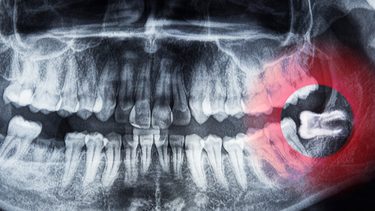

Biến chứng muộn sau ba đến mười bốn ngày

Khi vết nhổ bước vào giai đoạn lành mô mềm, một số vấn đề muộn có thể xuất hiện như:

- Ổ khô còn gọi là alveolar osteitis xảy ra khi cục máu đông không hình thành hoặc bị bong ra khỏi ổ răng. Người bệnh thường đau nhói và kéo dài đến tận tai hoặc thái dương.

- Nhiễm trùng ổ răng khiến vùng nhổ sưng nóng đỏ đau có mủ và có thể gây sốt.

- Tổn thương thần kinh kéo dài dẫn đến tê môi hoặc mất cảm giác một phần ở lưỡi trong thời gian nhiều tuần.

- Ảnh hưởng đến răng kế cận như sâu răng hoặc tụt lợi do vị trí tương tác với răng khôn.

- Một số biến chứng hiếm gặp hơn như thông xoang hàm sau nhổ răng hàm trên hay tình trạng mỏi và hạn chế vận động khớp hàm.

Những tình trạng trên đều nằm trong nhóm những biến chứng sau khi nhổ răng số 8 khiến thời gian hồi phục lâu hơn và người bệnh dễ cảm thấy lo lắng.